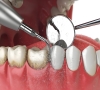

洗牙是通過專業器械去除牙齒表面及牙齦溝內的牙菌斑、牙結石等,達到預防牙周疾病、改善口腔衛生的作用。不同的洗牙方式有什麼區別呢?接下來,深圳三康牙醫為您解答。1.... [詳細]

洗牙是維護口腔健康的重要方式。定期洗牙的好處有以下幾種:1. 有效清除牙菌斑和牙結石平時刷牙很難完全清除掉牙縫等部位的牙菌斑,長期堆積會形成牙結石。洗牙可以通過... [詳細]

當咖啡漬悄悄附著在牙面,當牙結石不知不覺得堆積,很多人開始關注洗牙。然而,五花八門的洗牙方式讓人眼花繚亂,這些洗牙方式到底有什麼不同,哪種才是最適合自己的?今天... [詳細]